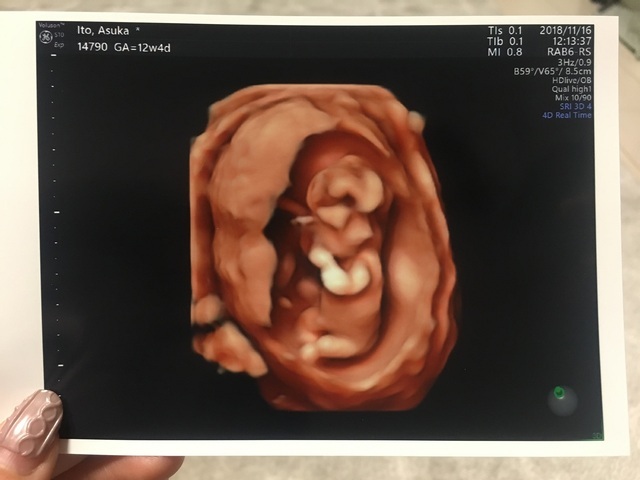

12週4日(12w4d・性別不明)|ななみかりん さん(30歳)

エコー写真撮影時のエピソード:

はじめての4dエコーです!ついこの前まで、豆粒みたいで小さい固まりだった赤ちゃんが、人の形をしているのを見て感激したことを、よく覚えています。妊娠検査薬で陽性が出て以降初めて、妊娠しているということを強く実感した思い出のエコー写真です。旦那もすごく喜んでくれて、エコー写真をずっと見ていました。